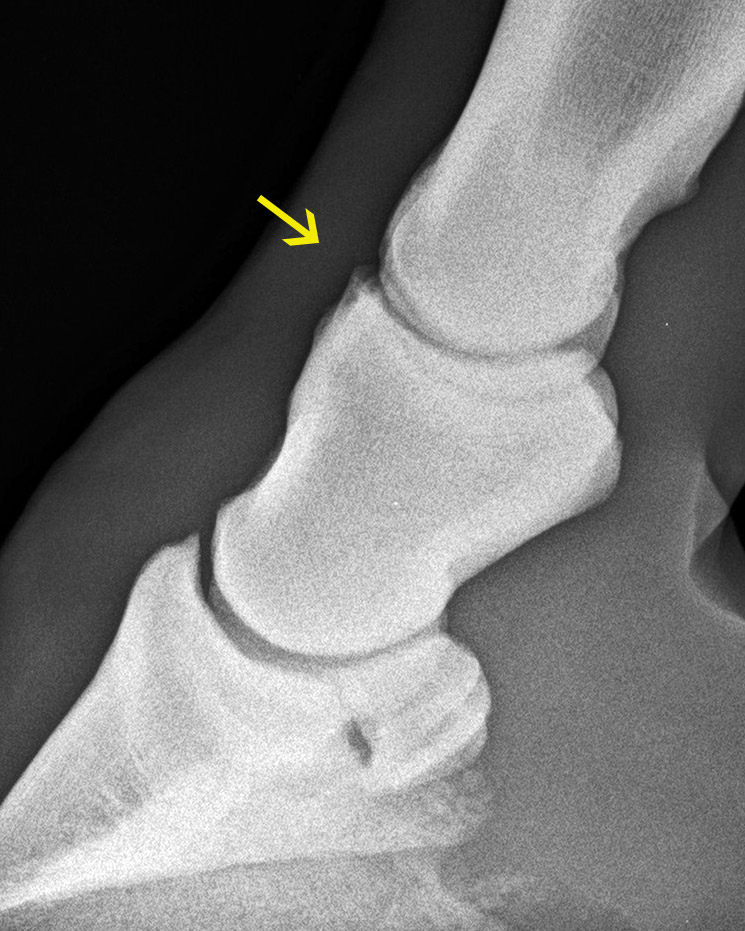

Krongelenksarthrose (gelber Pfeil)